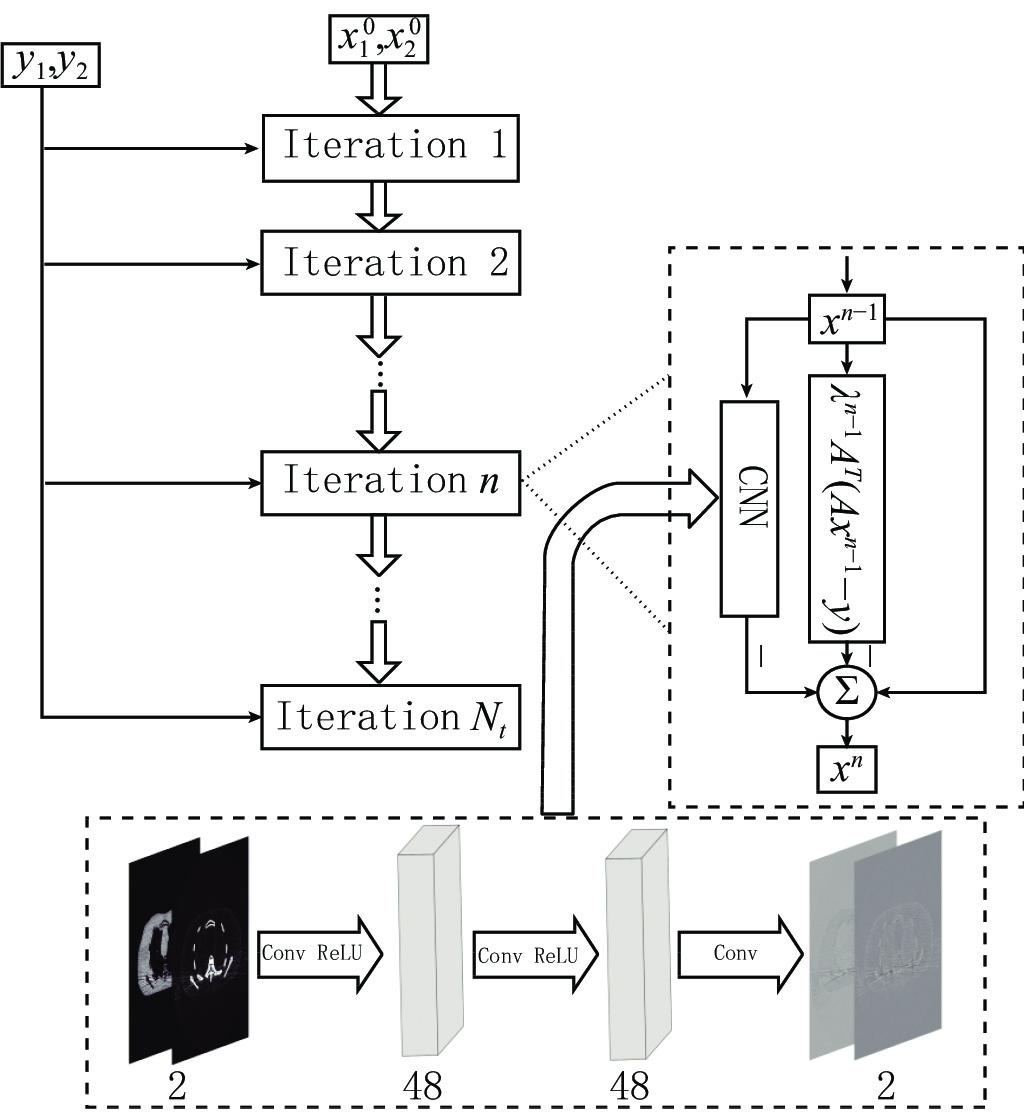

$$ \begin{array}{*{20}{l}} &Q\left( {{{\boldsymbol{x}}^t}} \right) = f_L^t \Biggl({18}{{\rm{ReLU}}\bigg( {f_{L - 1}^t\bigg( { \cdots {\rm{ReLU}}\Big( {f_1^t} \Big)} \bigg)} \Bigg)} \Biggr)\\ &f_1^t = {\boldsymbol{W}}_1^t * {{\boldsymbol{x}}^t} + {\boldsymbol{b}}_1^t{\text{ }} \\ &f_l^t = {\boldsymbol{W}}_l^t\Bigg( {{\rm{ReLU}}\bigg( {f_{l - 1}^t} \bigg)} \Bigg) + {\boldsymbol{b}}_l^t\;\;\;\;{\text{ }}\Big( {l = 2,3, \cdots ,L} \Big) \end{array}, $$ (5) ${\boldsymbol{W}}_{l}^{t}(l=\mathrm{1,2,}\cdots ,L)$ 是包含$ {n}_{l} $ 个卷积核的权重,其中卷积核大小为$ {\mathit{s}}_{l} $ ,${\boldsymbol{b}}_{l}^{t}$ 是偏置。$ * $ 和ReLU(·)分别为卷积运算和激活函数,L为网络的层数。图1显示了本文的深度迭代框架。${\lambda }^{t-1}{{\boldsymbol{A}}}^{{\rm{T}}}({\boldsymbol{A}}{\boldsymbol{x}}^{t-1}-{\boldsymbol{y}})$ 对应于数据保真项,${\boldsymbol{x}}^{t-1}$ 和${\boldsymbol{x}}^{t}$ 之间利用shortcut连接,整体的架构是一个保留结构细节并加速训练的残差网络。2.2 网络训练

${\boldsymbol{x}}^{0}$ 。迭代次数为200次,前100次学习率为10−4,后100次迭代学习率为10−5。使用神经网络工具箱MatConvNet进行了训练。算法编程环境为:Ubuntu 16,处理器为3颗Intel(R) xeon(R) E5-2640 v4 @ 2.40 GHz,内存32 G,显卡为Tesla K80。影响分解质量的参数包括卷积核$ \left\{{n}_{1},{n}_{2},{n}_{3}\right\} $ 的数量、卷积核的大小$ \left\{{s}_{1},{s}_{2},{s}_{3}\right\} $ ,以及总迭代次数$ {N}_{i} $ 。上述所有参数在本实验中均手动设置。本文中,通过固定其他参数,扰动其中一个参数来得到合适的网络配置为$ {n}_{1}={n}_{2}= 48$ ,${n}_{3}=2$ ,${s}_{1}= {s}_{2}= {s}_{3}=$ 3×3,$ {N}_{i}= 13$ 。3. 实验